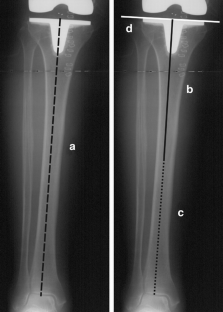

Anteroposterior radiographs that included the whole tibia were taken before and after 75 total knee arthroplasties in 48 patients. The same tibial extra-medullary alignment guide system was used in every knee. The average tibial component alignment was 0.4 (SD 2.5, range −4.9 to 6.4) degrees of valgus post-operatively. 59 tibial components (78.7%) had a tibial cut within 3 degrees from being perpendicular to the mechanical axis, ten were too valgus (13.3%) and six were too varus (8%). The chance of the tibial components becoming too varus was higher if there was lateral tibial bowing, compared with no tibial bowing (p = 0.048). A smaller lateral width of the leg increased the chance of the tibial components becoming too valgus (p = 0.047).

Fig. 1